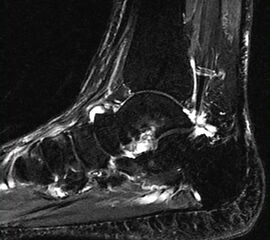

Diagnostische Methode der Wahl ist das MRT, das eine sichere Diagnosestellung erlaubt. Dabei kommt es  im betroffenen Knochen zur signalarmen Darstellung in der T1-Wichtung während T2 gewichtete Darstellungen als Folge des Ödems mit einer  Signalanreicherung in den betroffenen Skelettabschnitten und oft auch in den benachbarten Weichteilen imponieren

10.